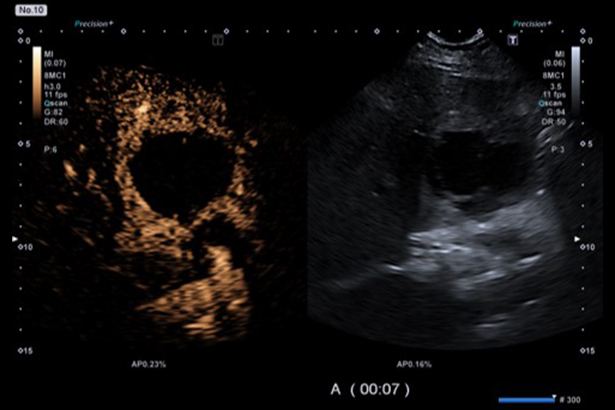

讓您在廣泛的臨床應用,包括一系列的特殊檢查中獲得灌注的動態信息。